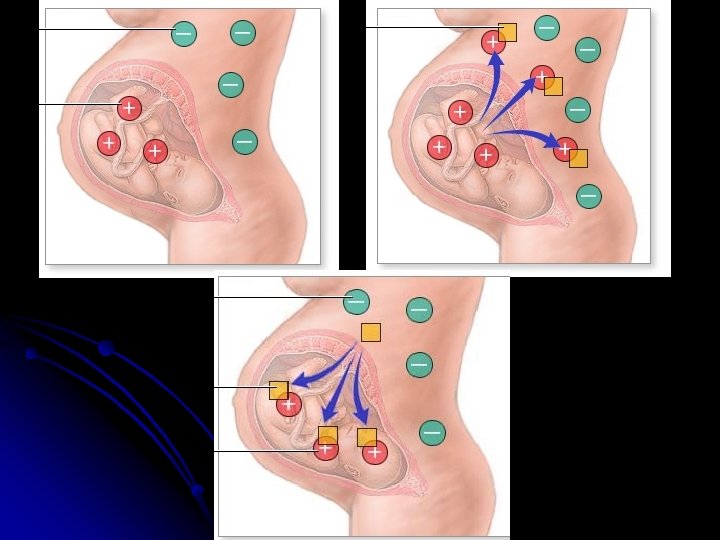

Two mechanism are proposed for sensitization : *sensitization ? ? Rh –ve patient are exposed to Rh-Ag 1 - Occurrence of undetected placental leak of fetal RBCs into the maternal circulation During pregnancy 2 - “ Grandmother theory “

*In general two exposures to Rh antigen Are required to produce any significant sensitization unless the first exposure is massive. *The initial response to exposure to Rh antigen is production of Ig. M for short period of time

Pathogenesis Of Rh Isoimmunisation Rh Negative Women Rh -ve Fetus No problem Man Rh positive (Homo/Hetero) Fetus Mother previously sensitized Secondary immune response ? Iso-antibody (Ig. G) Fetus Haemolysis Rh positive Fetus Rh+ve R. B. C. s enter Maternal circulation Non sensitized Mother ? Primary immune response Fetus unaffected, 1 st Baby usually escapes. Mother gets sensitised?